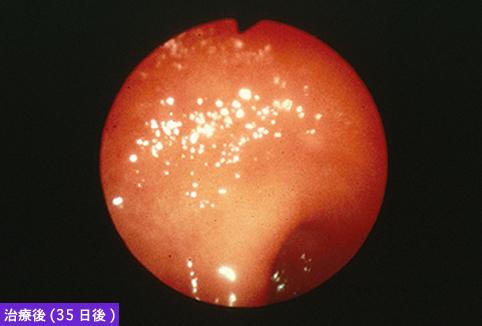

Disentería Amebiana del Colon, que tuvo la formación principal en su posición inferior

Enfermedad Inflamatoria - Ulcerativa/Disentería Amebiana

colon/recto

Endoscopia

1 - 9